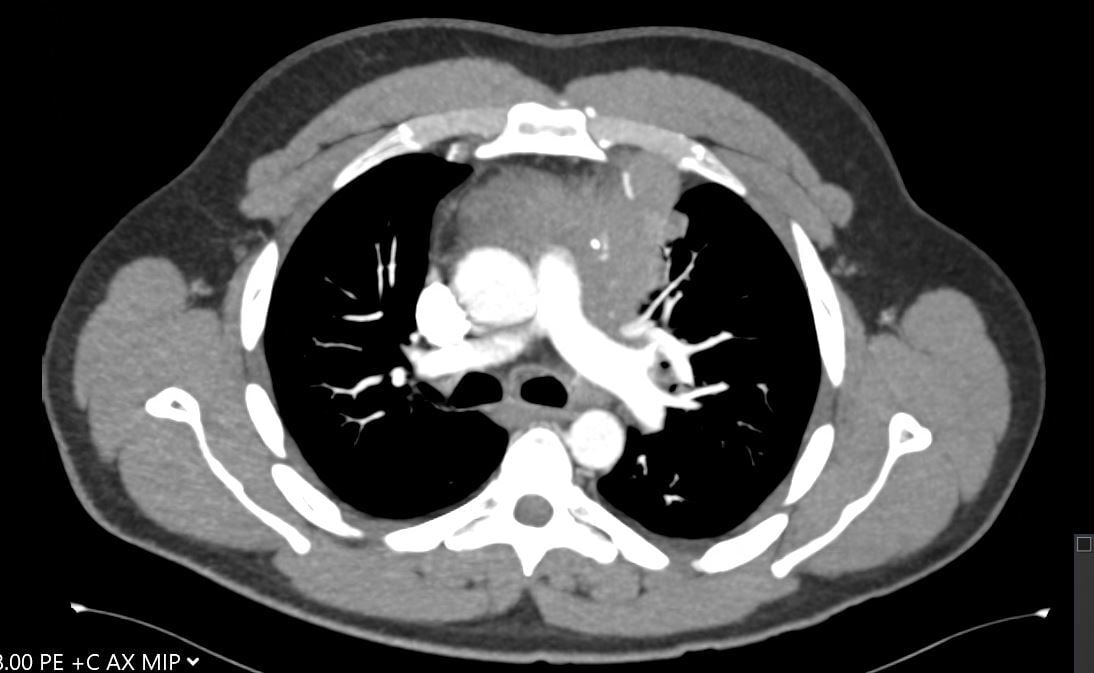

A 30-year-old man presents with dyspnea and is found to have an anterior mediastinal mass, as well as supraclavicular lymphadenopathy; biopsy of the mass is consistent with thymic carcinoma. Imaging shows his anterior mediastinal mass, lung and diaphragmatic lesions consistent with metastatic malignancy, and probable pericardial involvement with small pericardial effusion (Figures 1, 2, 3, and 4).

Fig. 1: CT image showing large mediastinal mass found to be thymic carcinoma. -